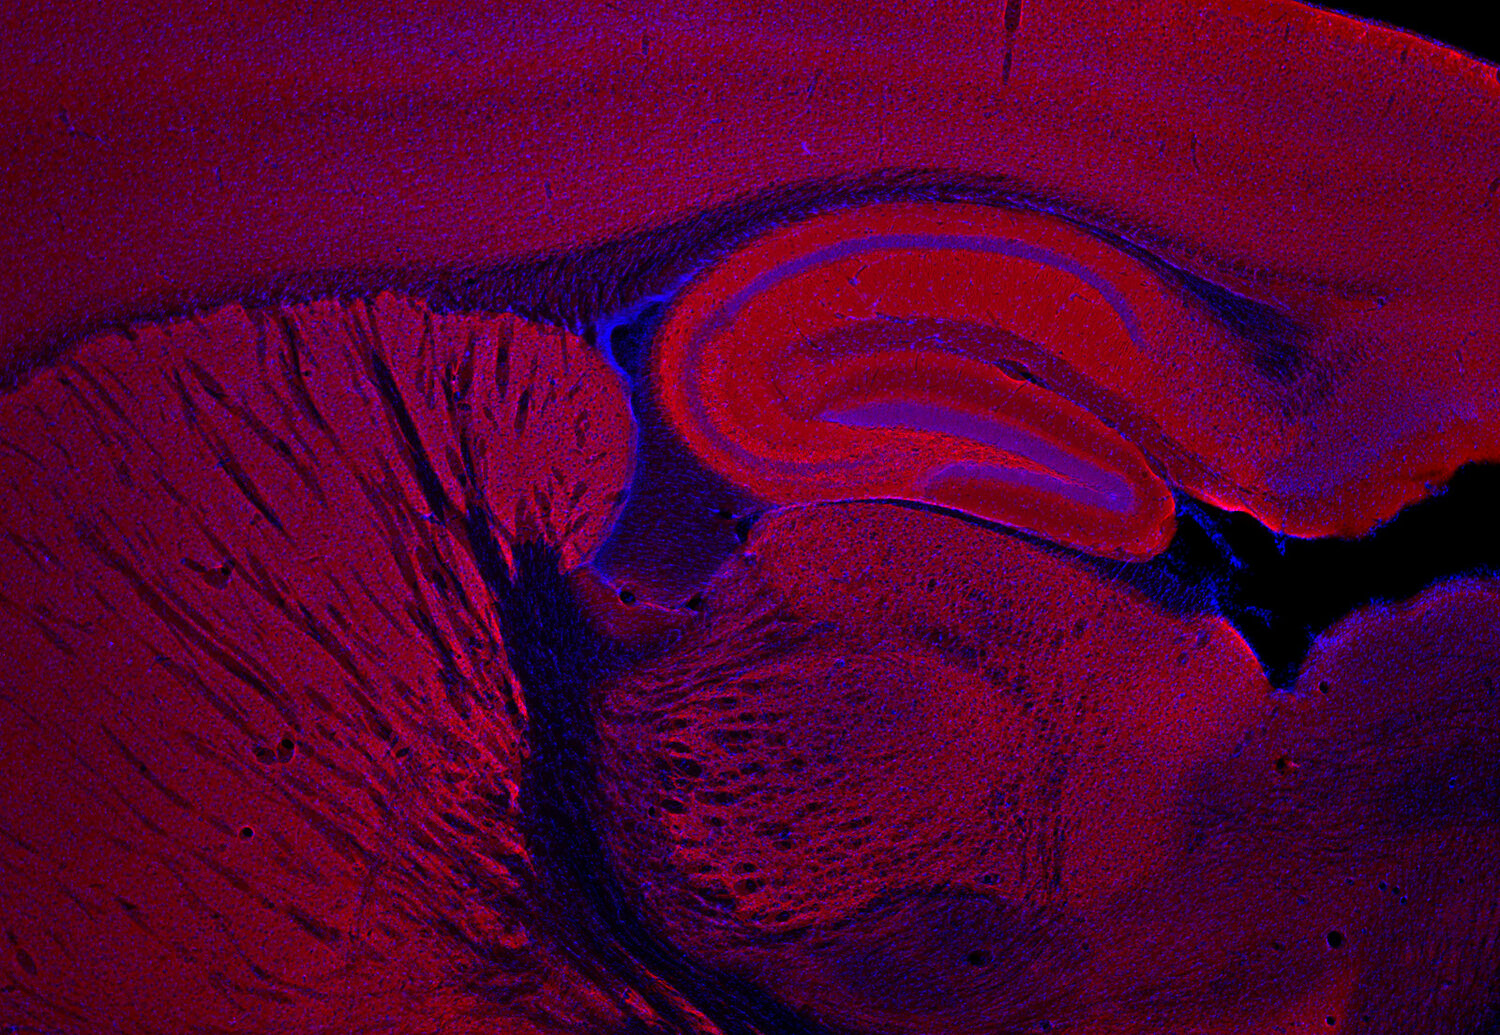

IHC: 1 : 500 gallery

Immunohistochemistry (IHC) on 4% PFA perfusion fixed tissue with 24h PFA post fixation. Immunoreactivity is usually revealed by fluorescence or a chromogenic substrate. Some antibodies require special fixation methods or antigen retrieval steps. For details, please refer to the ”Remarks” section.